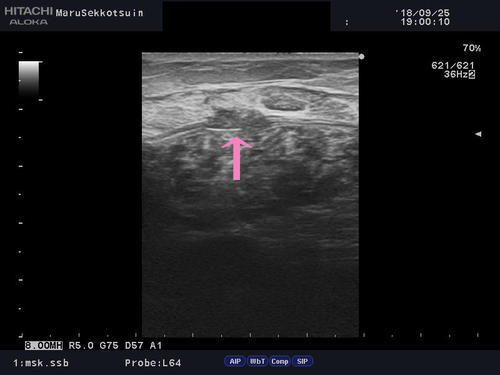

しっかり問診、触診をして、負傷箇所を確定し、深さ・広さを確認する為にエコー検査。

結果、ふくらはぎ肉離れ、好発部位である「腓腹筋内側頭部の肉離れ」でございました。

calf2.jpgcalf.jpg